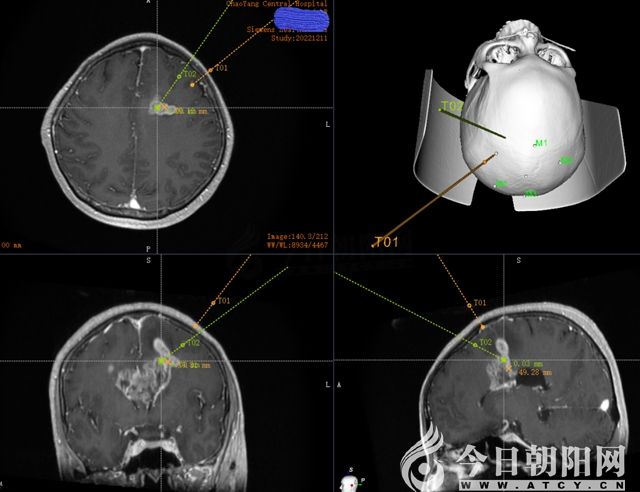

術(shù)前機器人精準規(guī)劃手術(shù)路徑,避開重要神經(jīng)和血管

機器人精確定位,穿刺更精準,手術(shù)時間短、出血少。